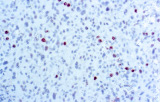

Estudos recentes destacam o valor diagnóstico das proteínas do complexo SWI/SNF, particularmente ARID1B, na identificação de malignidades ginecológicas desdiferenciadas e indiferenciadas – tumores agressivos com mau prognóstico. A IHQ de ARID1B oferece elevada especificidade e está cada vez mais integrada em painéis diagnósticos para melhorar a precisão. Painéis com marcadores adicionais também apoiam a diferenciação de sarcomas uterinos, aumentando a exatidão diagnóstica. Evidência emergente sugere que ARID1B pode representar um alvo terapêutico potencial no carcinoma ovárico de células claras, embora as aplicações clínicas permaneçam em fase investigacional.

Anticorpos primários contra recetor de estrogénio (ER), recetor de progesterona (PR), HER2 e Ki-67 continuam a ser a pedra angular da classificação e decisões terapêuticas no cancro da mama. Estes anticorpos estão validados clinicamente e marcados CE/IVD para garantir deteção fiável e reproduzível de biomarcadores – crucial para orientar terapia hormonal e estratégias de tratamento direcionado.